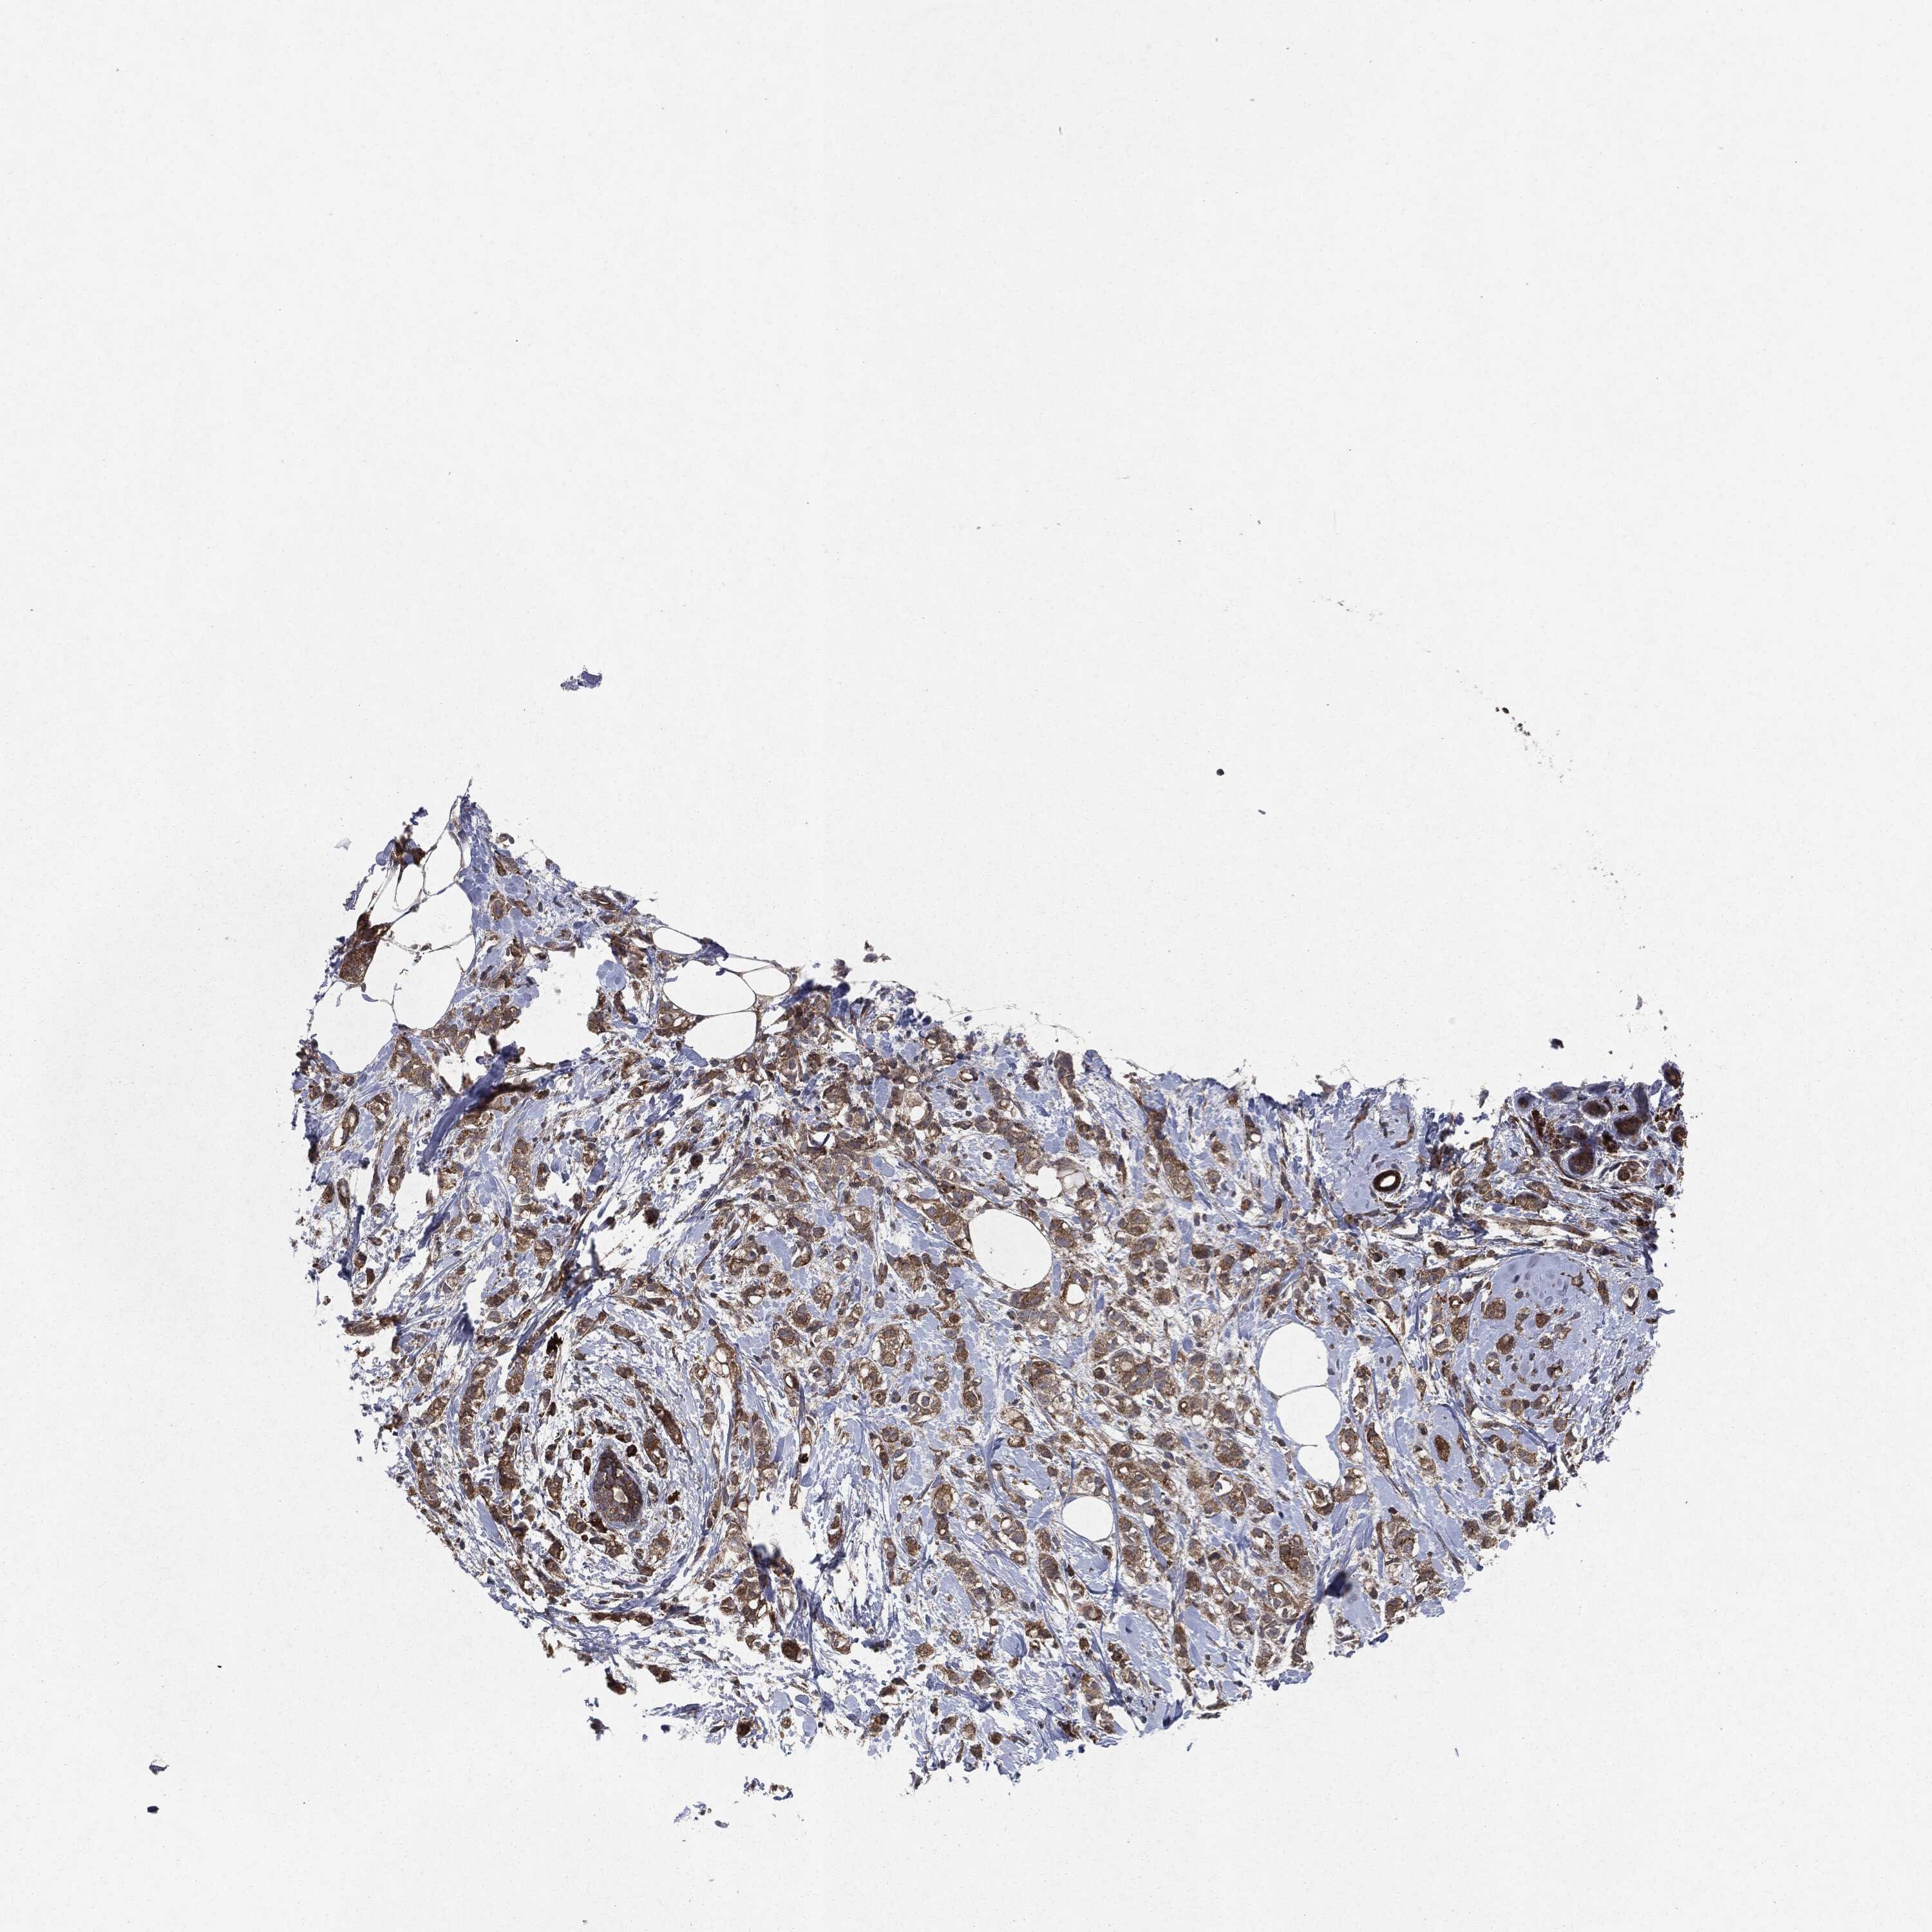

BRCA TCGA BRCA VALIDATION PROTEIN EXPRESSION